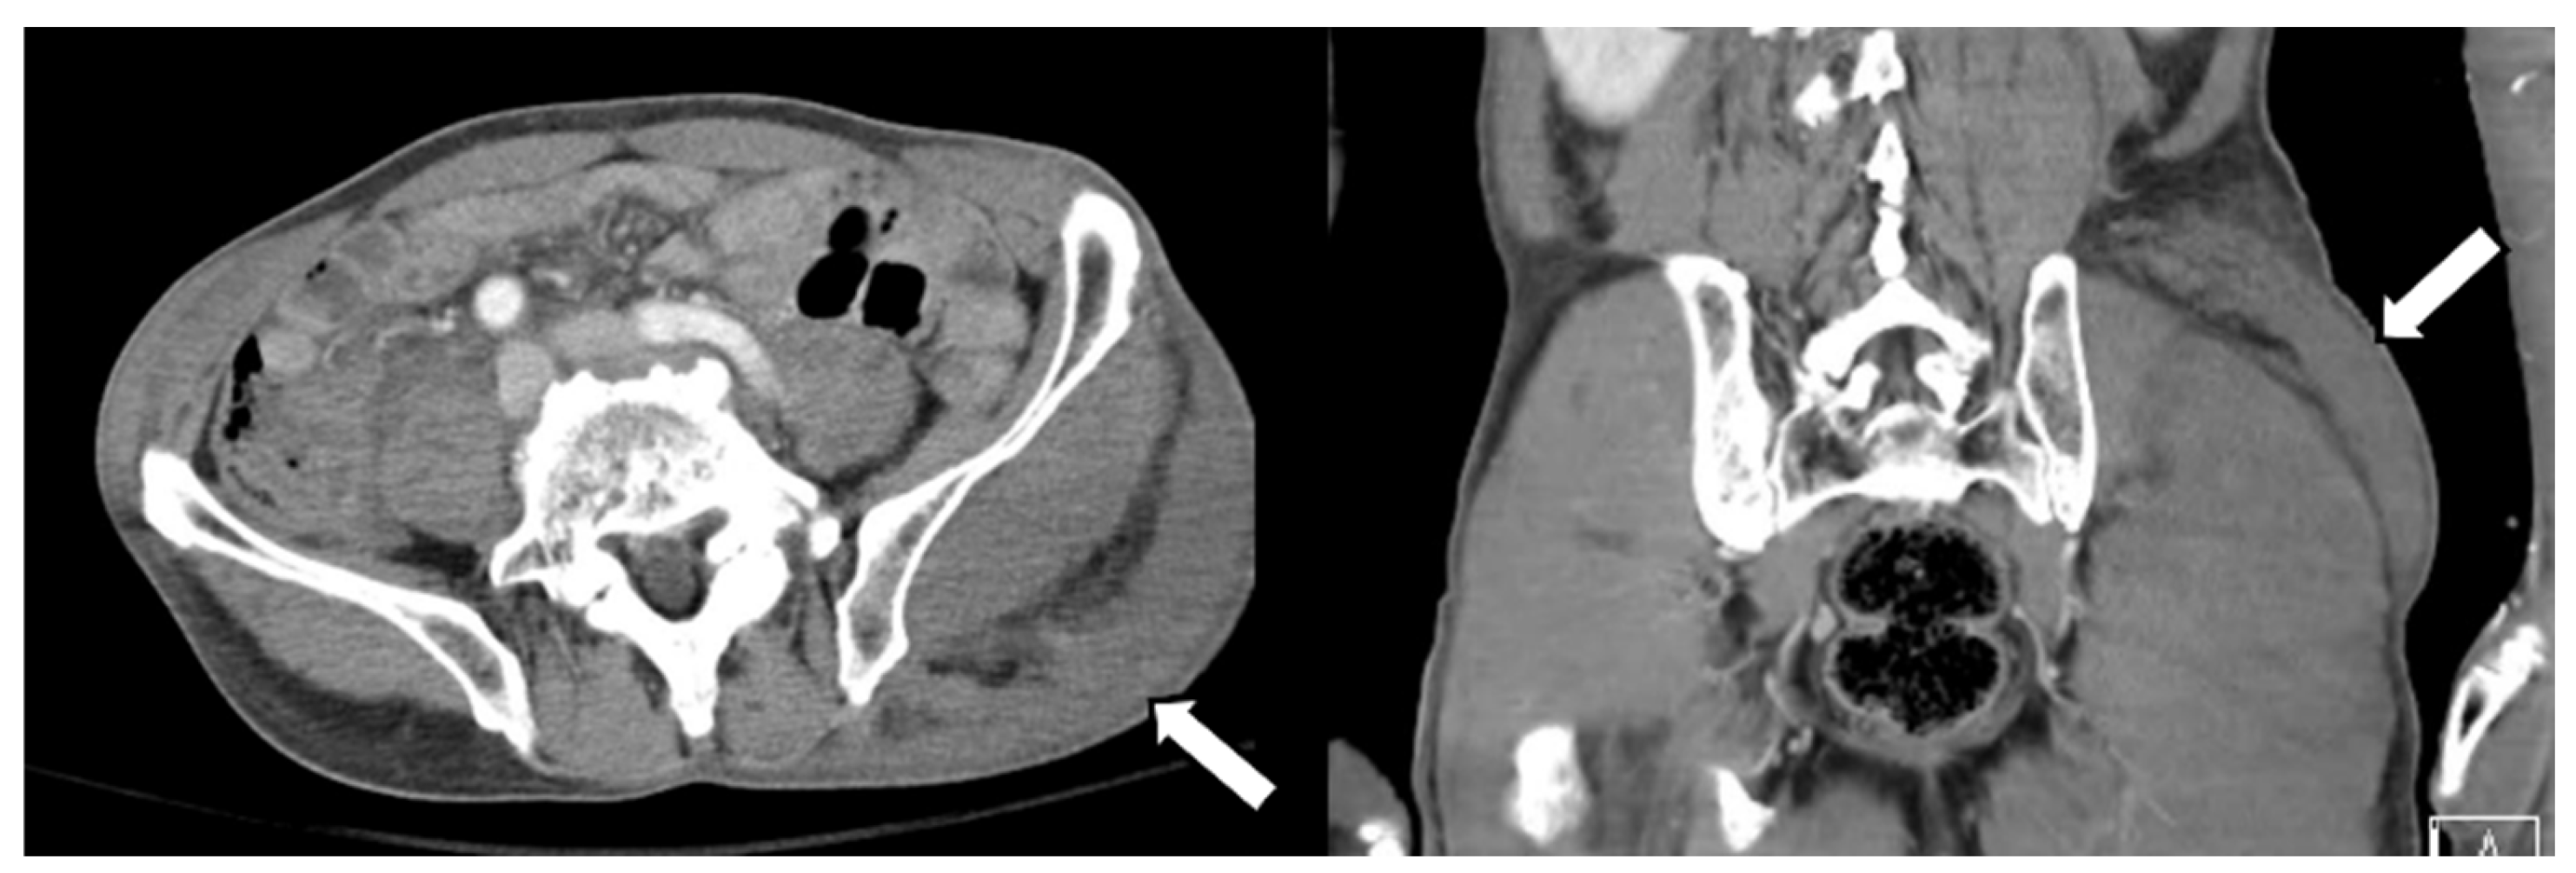

A 77-year-old man visited our hospital’s emergency room with severe low back pain. A few hours ago, while towing a cart, he was in a car accident wherein a vehicle collided behind him. The patient had a history of coronary artery disease for which he was taking an anticoagulant. Several tests were performed, including a CT and MRI of the spine. There were multiple transverse processes, and vertebral body fractures in the examination, so conservative management was performed. Additionally, the MRI image of the lumbar spine showed a curvilinear shape lesion with increased signal intensity in the left buttock region (Figure 1). Similar findings to the above were also seen on abdominal CT (Figure 2). Thus, we considered a subcutaneous edema or hematoma for this finding.

Figure 1. Magnetic resonance imaging (MRI) of the buttock. MRI revealed a well-defined mass in the left buttock. The mass showed a heterogeneously higher signal intensity than the skeletal muscle on T2-weighted images.